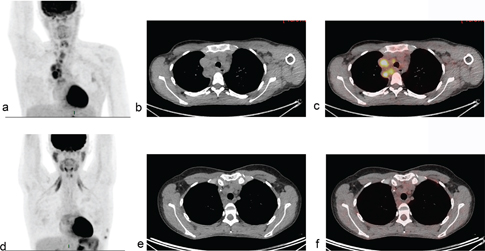

Fig 2

Figure 2. A young woman with a history of progressive swellings, dyspnea, and fever. Biopsy revealed Hodgkin lymphoma. Abnormal FDG-uptake at baseline PET/CT (a,b,c) was confined to enlarged clavicular and mediastinal lymph nodes, i.e., disease stage 2. Interim PET/CT (d,e,f) after two cycles of ABVD (doxorubicin, bleomycin, vinblastine, and dacarbazine) was coherent with complete metabolic response (Deauville Score 2) although lymph nodes remained enlarged on CT scan.

Fig 3

Figure 3. A young woman with Hodgkin lymphoma, stage II. Baseline FDG PET/CT (a). Interim PET/CT (b) performed after two cycles of ABVD (doxorubicin, bleomycin, vinblastine, and dacarbazine,) revealed partial metabolic response with residual FDG-uptake above liver uptake (lymphoma SUVmax=8.6, liver SUVmax=2), classified as DS 4.

A common language for assessing metabolic response by PET/CT is necessary to ensure that the treatment decisions are reproducible. The international harmonization criteria from 2007 proposed a dichotomous scoring system where mediastinal blood pool activity was recommended as the reference background activity to define PET positivity for a residual mass greater or equal to 2 cm in greatest transverse diameter, whereas background update was to be used for assessment of smaller lesions (28). However, dichotomous scores in lymphoma proved suboptimal. Response-adapted treatment strategies based on interim PET/CT should enable tailoring the risk of false positive/false negative assessments to the question being asked in the trial, which can be done using more granular response reporting (29). The Deauville 5-point score (DS) is now the standard for reporting PET/CT response assessment in lymphoma (Figure 2 and 3) (7). DS was conceived to graduate the intensity of 18F-Fluoro-deoxy-glucose (FDG) uptake in previously identified lymphoma lesions relative to the liver uptake. DS 1 and 2 represent a FDG uptake lower than that of liver, uptake DS 3 represents an intensity of uptake up to that of liver, and DS 4 and 5 represent different degrees of FDG uptake above liver level and new lesions (score 5) (7). For interim and end-of-therapy response assessment in HL, a scores between 1 and 3 are conventionally considered as complete metabolic response (Figure 2) whereas DS 4 or 5 represent active HL (Figure 3) (7). Several studies have shown that the Deauville score is high prognostic in HL using DS 1–3 to define a complete metabolic response (CMR) and DS 4–5 as non-response. In two recently finalized trials of PET-guided de-escalation strategies (HD16 and D18) conducted by the German Hodgkin Study Group, the trials were designed to use DS 1–2 (above the mediastinum) as negative (or equivalent), but further analyses of these trials showed that residual uptake above liver level (DS 4–5) was better in predicting outcomes (3032). In the HD16, 5-year PFS was 93.2% among PET-2-negative patients and 88.4% in PET-2-positive patients (P = .047) when using DS3+ as definition of a positive PET/CT, but when using liver cutoff (DS 4+) for PET-2 positivity, 5-year PFS was 93.1% for PET negative patients vs 80.9% for PET positive patients (P = .0011) (30). In post-hoc analyses of HD18, DS4 was the only risk factor for inferior overall survival in a cohort of patients with DS 1–4 after two cycles of BEACOPP escalated after adjustments for other risk factors (32). The timing of interim PET/CT in HL is conventionally after two courses of chemotherapy, but a negative PET/CT after 1 cycle also has a very high negative predictive value (2-year PFS 98%) and is currently used in clinical trials of very early PET/CT adapted treatment strategies (NCT03517137) (33).